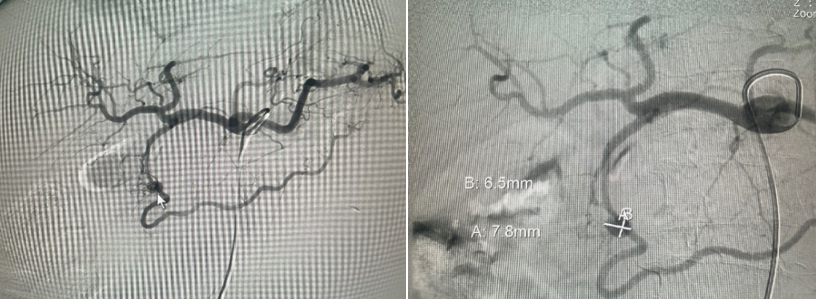

Ghi nhận tại khoa hồi sức tích cực: Bệnh nhân được hồi sức tích cực (có dùng vận mạch), tuyền tổng cộng 5 đơn vị hồng cầu khối, 3 đơn vị plassma, chụp CT bụng có thuốc cản quang, nội soi dạ dày cấp cứu ghi nhận dạ dày sạch, miệng nối không thấy chảy máu, trong nang có nhiều máu đông.

Hình 3 và 4. Hình ảnh chảy máu trong nang (nội soi) và CT scan ngày 15/12